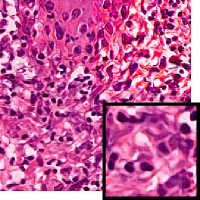

We demonstrate our WSI creation workflow on Leishmaniasis cases, as shown in Figures 1 and 4. An expert pathologist reviewed the cases and annotated granulomas as well as LD bodies on the stitched images and our generated images in Figure 4. To show generalizability of our approach, we also show results on core biopsies of breast, duodenum, stomach, liver, and lymph nodes (Figure 5).

| Breast | Duodenum | stomach | liver | lymph node | |||||